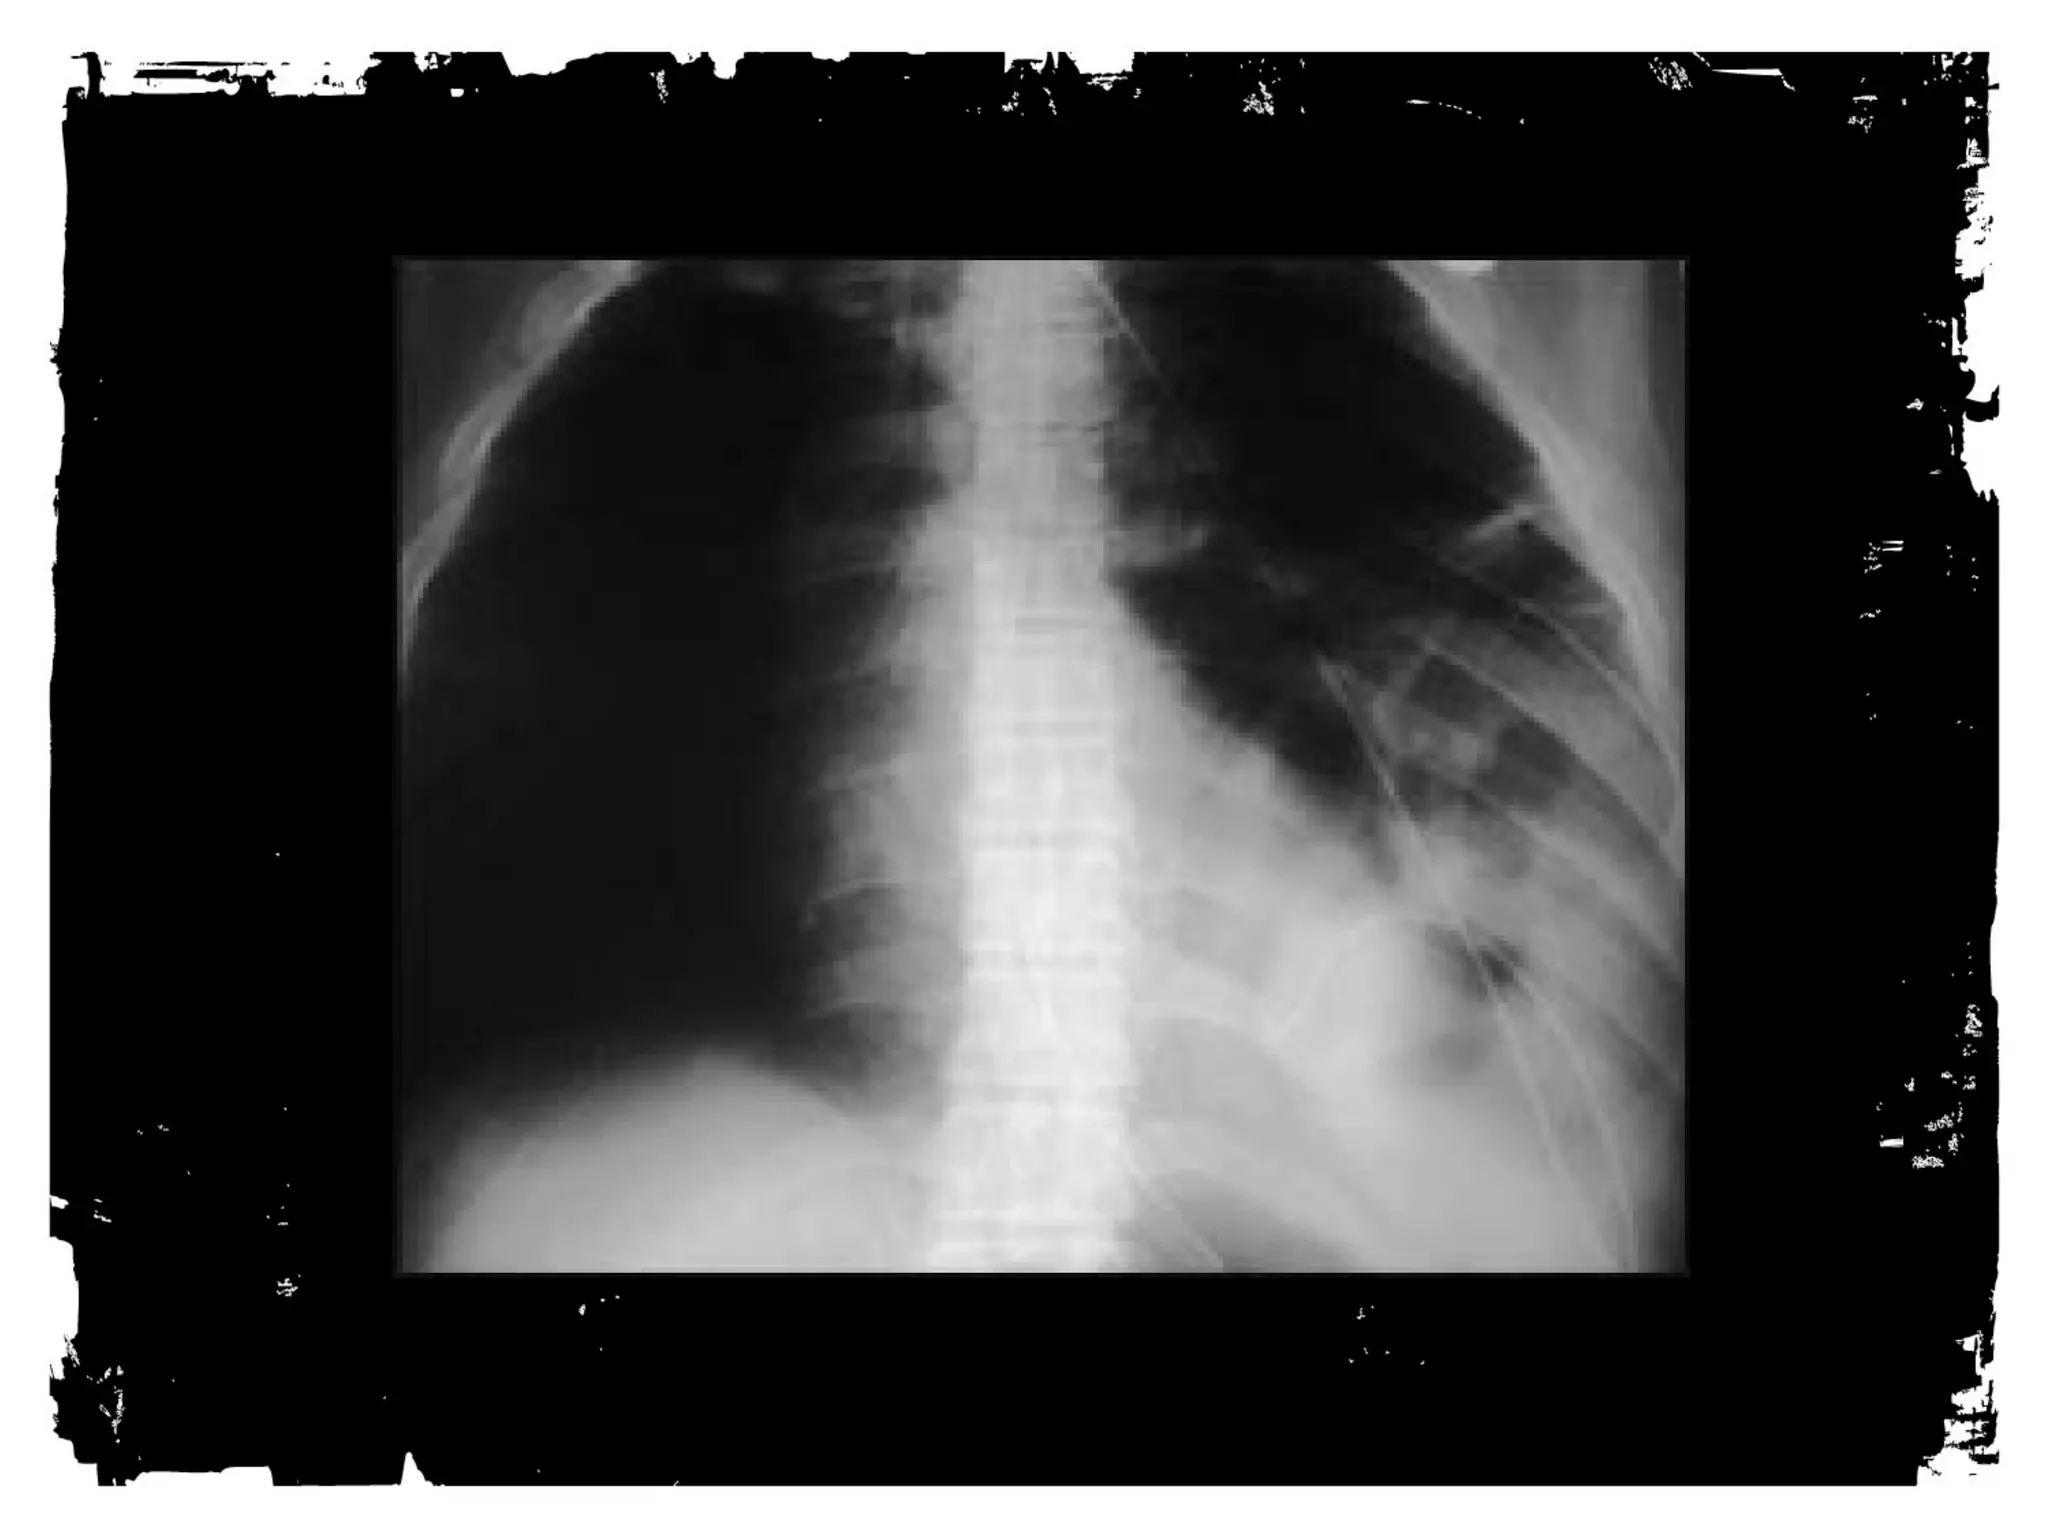

After chest trauma, imaging plays a key role for both,

the primary diagnostic work-up, and the secondary

assessment of potential treatment. Despite its well-known

limitations, the AP chest radiograph remains

the starting point of the imaging work-up. Adjunctive

imaging with CT, that recently is increasingly often

performed on MDCT units, adds essential

information not readily available on the CXR. This

allows better definition of trauma-associated thoracic

injuries not only in acute traumatic aortic injury, but

also in pulmonary, tracheobronchial, cardiac,

diaphragmal, and thoracic skeletal injuries.

Trauma Chest Radiograph

• Usually AP, often supine,

frequently in poor inspiration.

• So, a challenge to interpret.